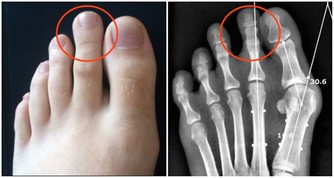

骨科醫生不希望你:總是坐軟沙發

沙髮質地太軟,人坐上去,腰椎缺乏足夠支撐,容易骨盆向後傾斜。

久而久之會導致腰部肌肉勞損、骨質增生,甚至誘發腰椎間盤突出。

最好坐有靠背的硬椅子,臀部充分接觸椅面,腰背部貼緊椅背,使腰背部肌肉更放鬆,腰椎間盤壓力也較小。